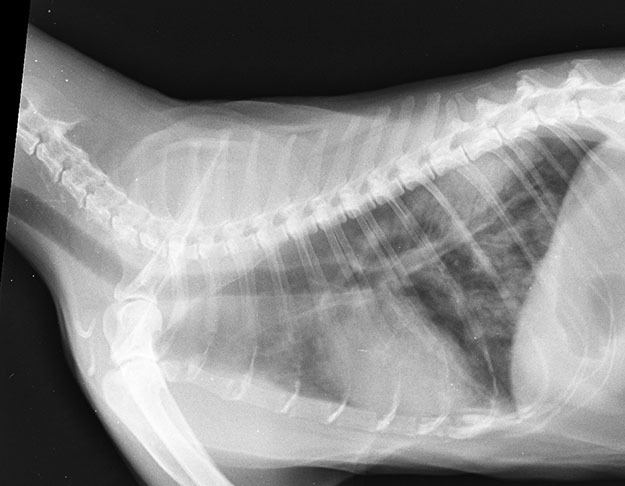

Contamos con equipo radiológico digital veterinario para obtener una mucho mejor calidad de imagen y poder así realizar un diagnóstico más acertado en nuestros pacientes, este servicio está disponible las 24hrs y no es necesario realizar cita.

Todas las interpretaciones las realizan médicos veterinarios expertos en el área.

RADIOLOGÍA Y

ULTRASONIDO